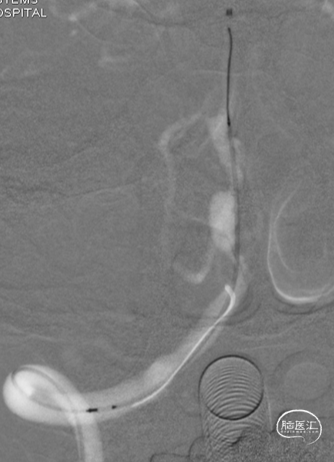

术后即刻DSA。

术后即刻稀释造影:“拉直”可见支架贴壁良好。